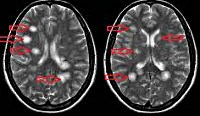

G04 Энцефалит, миелит и энцефаломиелит